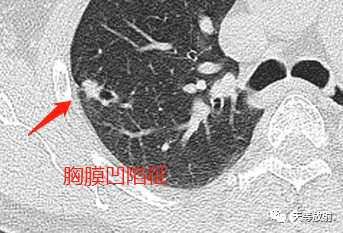

实性结节呈分叶状改变,邻近胸膜增厚,有牵拉改变,凹陷征。